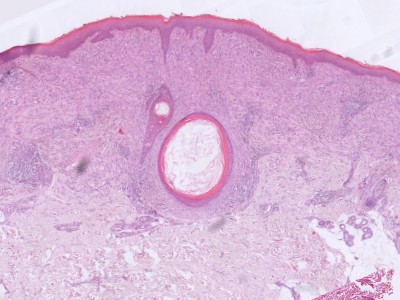

PA: Het karakteristieke PA kenmerk van Spitz tumoren

is de aanwezigheid van grote

spoelvormige cellen en/of

epithelioide cellen (melanocyten die lijken op keratinocyten).

Deze cellen zijn meestal gelegen in nesten hoog in de dermis, soms in de retelijsten

van de epidermis, soms in allebei. Er zijn verschillende histologische en morfologische

varianten van Spitz naevi, afhankelijk van welke chromosomale afwijking (tyrosine

kinase fusies, HRAS of MAP3K8 mutaties) er aanwezig is. Zie voor de correlatie

tussen de genetische afwijking, de klinische presentatie, en het histologisch

beeld het overzichtsartikel van Urso C. uit 2023.

De klassieke benigne

Spitz naevi zijn scherp begrensde symmetrische wigvormige laesies opgebouwd

uit grote junctionele (op de overgang epidermis-dermis) en dermale nesten van

spoelvormige en/of epithelioide melanocytaire cellen. Deze cellen zijn groot,

met veel bleek of matglas-achtig aankleurend cytoplasma en soms fijnkorrelig

pigment. Er is wat kern pleomorfisme, maar weinig of geen mitosen. De junctionele

nesten zijn loodrecht op de epidermis georiënteerd en vaak omgeven door spleetvormige

ruimten, dit zijn artefacten die ontstaan tijdens de bewerking van de coupe.

Melanocyten kunnen opstijgen in de epidermis (ascensie, synoniem pagetosis,

pagetoide verspreiding), meestal beperkt tot de onderste helft van de epidermis,

en transepidermale elininatie van melanocyten komt voor. Op de dermo-epidermale

overgang kunnen bij klassieke Spitz-naevi PAS-positieve eosinofiele hyaline

globuli voorkomen die

Kamino bodies worden genoemd.

Verder is er soms een perivasculair lymfocytair infiltraat. Zie ook de

ingescande

PA-coupe van de

afdeling

pathologie van de University of Toronto, en de ingescande coupes uit het

LUMC hier onder: